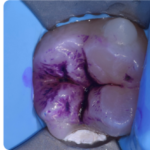

Solchi e fossette pigmentate affette da carie ed errori diagnostici: una possibile soluzione

Spesso quando ci si trova davanti a solchi occlusali e fossette pigmentate è difficile determinare con esattezza innanzitutto la presenza di una lesione cariosa e, in secondo luogo, il suo stadio. Quali approcci per una diagnosi corretta?

Il supporto della fluorescenza alla diagnosi visiva della lesione cariosa

Conoscere lo stato di attività di una lesione cariosa non è semplice: un valido supporto è rappresentato dalla fluorescenza, la proprietà fisica di alcuni batteri o tessuti di assorbire e in parte riflettere un fascio di luce incidente, restituendoci informazioni preziose.

La gestione clinica e operativa dei solchi e delle fossette pigmentate: il corso dedicato

La fluorescenza permette di fare diagnosi sulla presenza di lesione cariosa a livello del solco e fossetta pigmentata e altresì fornisce indicazione se la lesione cariosa - eventualmente presente – si presenta in una fase attiva, tendente alla cavitazione, oppure in una fase inattiva e stabile nella progressione. Un corso ci insegna come utilizzare questa tecnologia per una corretta diagnosi.